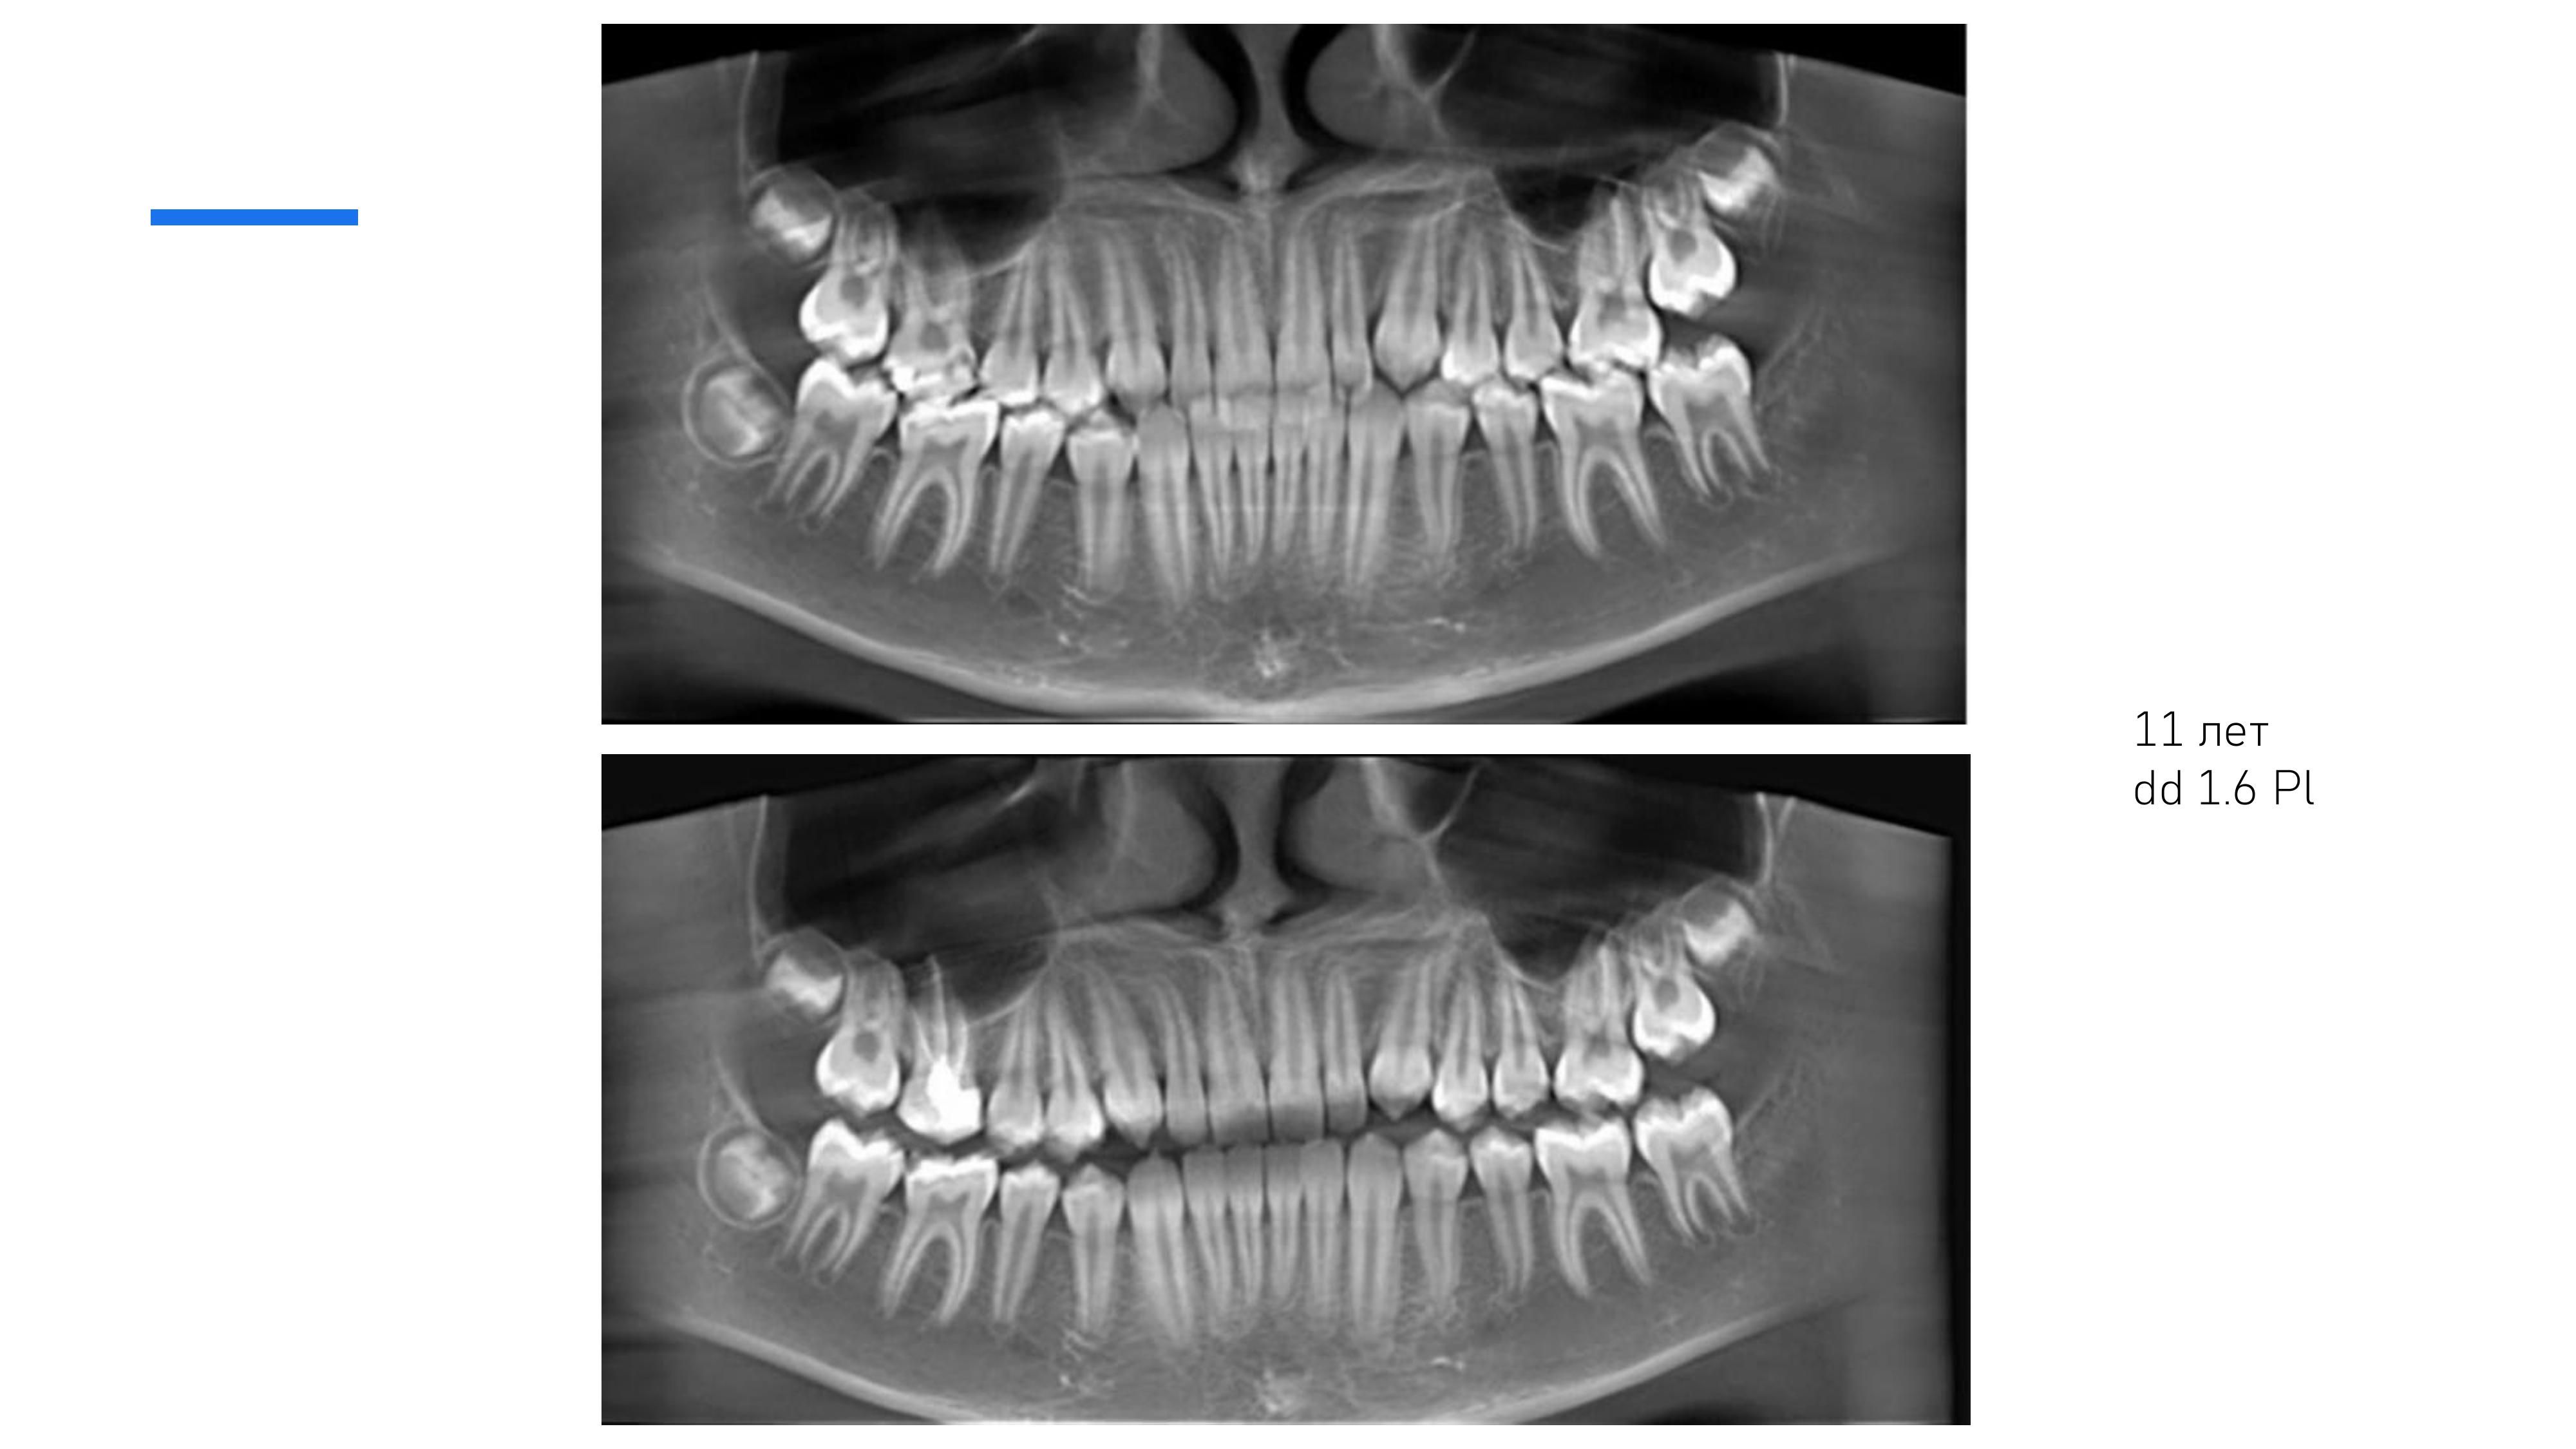

2. Анализ рентгеновских исследований, компьютерных томограмм.

6. Диагностика и лечение кариеса временных и постоянных зубов с использованием микроскопа, лечение пульпитов и периодонтитов временных и постоянных зубов.